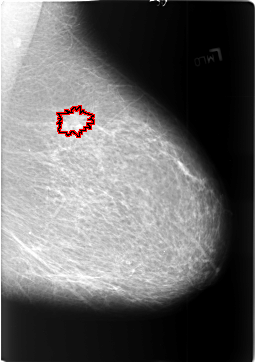

FILE: B_3391_1.LEFT_CC.OVERLAY

TOTAL_ABNORMALITIES 1

ABNORMALITY 1

LESION_TYPE MASS SHAPE IRREGULAR-ARCHITECTURAL_DISTORTION MARGINS SPICULATED

ASSESSMENT 4

SUBTLETY 4

PATHOLOGY MALIGNANT

TOTAL_OUTLINES 1

BOUNDARY